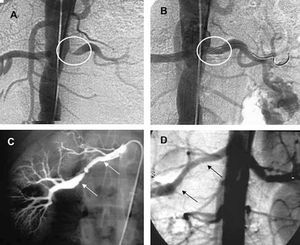

Thus, arteriography is indicated in those cases in which noninvasive studies are equivocal or there is high clinical suspicion and concomitant angiography must be performed (Figure 4).

Figure 4. Renal artery angiography showing marked stenosis in left renal artery (white circle) with mild poststenotic dilatation.

Doppler ultrasound has a sensitivity of up to 96% and a specificity of up to 98%.78 Although it does not enable direct functional assessment, it provides hemodynamic and sonographic information about the renal artery, the state of the parenchyma and renal anatomy, enhanced, unlike arteriography, with the use of ultrasound contrast agents79 (Figure 5). Although some authors propose it as the study of choice, it is an examiner-dependent technique that may prove impracticable in up to 20% of selected patients.61

Figure. 5. A: color Doppler ultrasound image of the stenosis depicted in Figure 4. B: increase in Doppler velocities in the region of the stenosis.